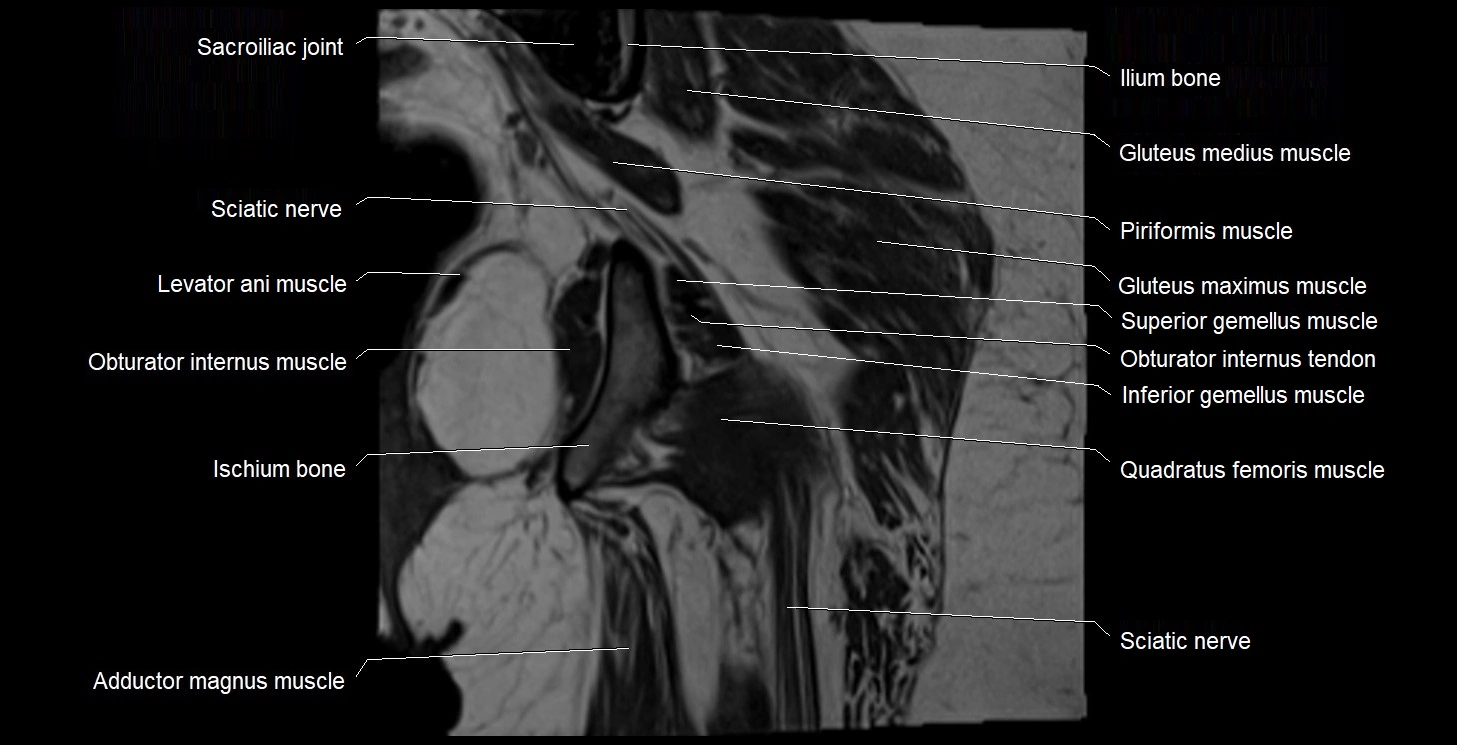

- Gluteus maximus muscle

- Gluteus medius muscle

- Ilium bone

- Inferior gemellus muscle

- Ischium bone

- Levator ani muscle

- Obturator internus muscle

- Obturator internus tendon

- Quadratus femoris muscle

- Sacroiliac joint

- Superior gemellus muscle